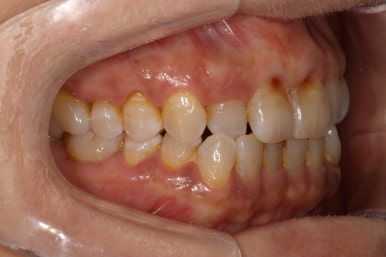

앞니의 치경부 마모가 눈에 띄긴 하지만, 전체적으로 쌓여있는 치석말고는 별 문제가 없었습니다.

화살표로 가리치고 있는 치아의 불편감을 호소하고 계셨습니다.

보시다시피, 아래턱 큰어금니의 씹는면에 약간의 충치가 있는바.. 일단 레진으로 떼우기로 치료계획을 세웠었죠.